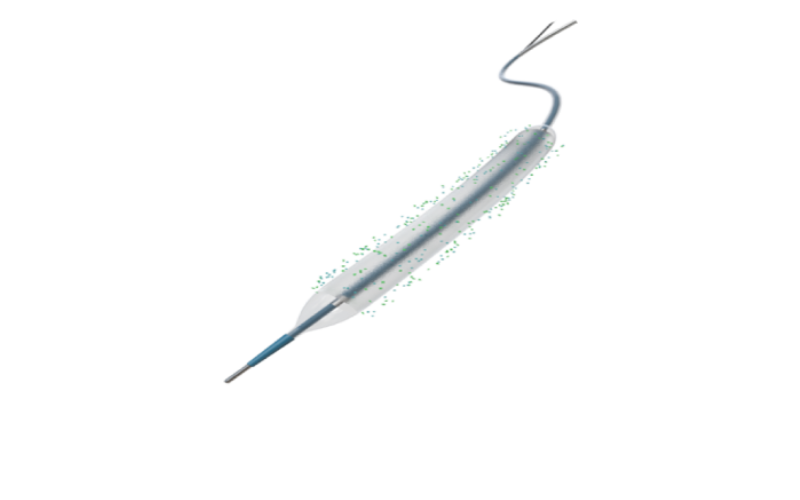

Lepu Dispositivos e Equipamentos Médicos de Alta Tecnologia

A Lepu Medical, líder em dispositivos médicos cardiovasculares, possui uma rede global de 190 subsidiárias. Com 214 produtos certificados pela CE e 34 aprovados pela FDA, a Lepu está construindo uma plataforma integrada que abrange dispositivos médicos, medicamentos, serviços de saúde e assistência médica móvel para atendimento cardíaco. A empresa está listada na Bolsa de Valores de Shenzhen (300003) e na Bolsa Suíça em 2009 e 2022, respectivamente.